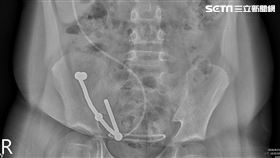

8歲童誤吞磁鐵 連吐7天肚子痛險死

台中8歲王小弟連續七天反覆出現嘔吐、肚子痛等症狀,起...